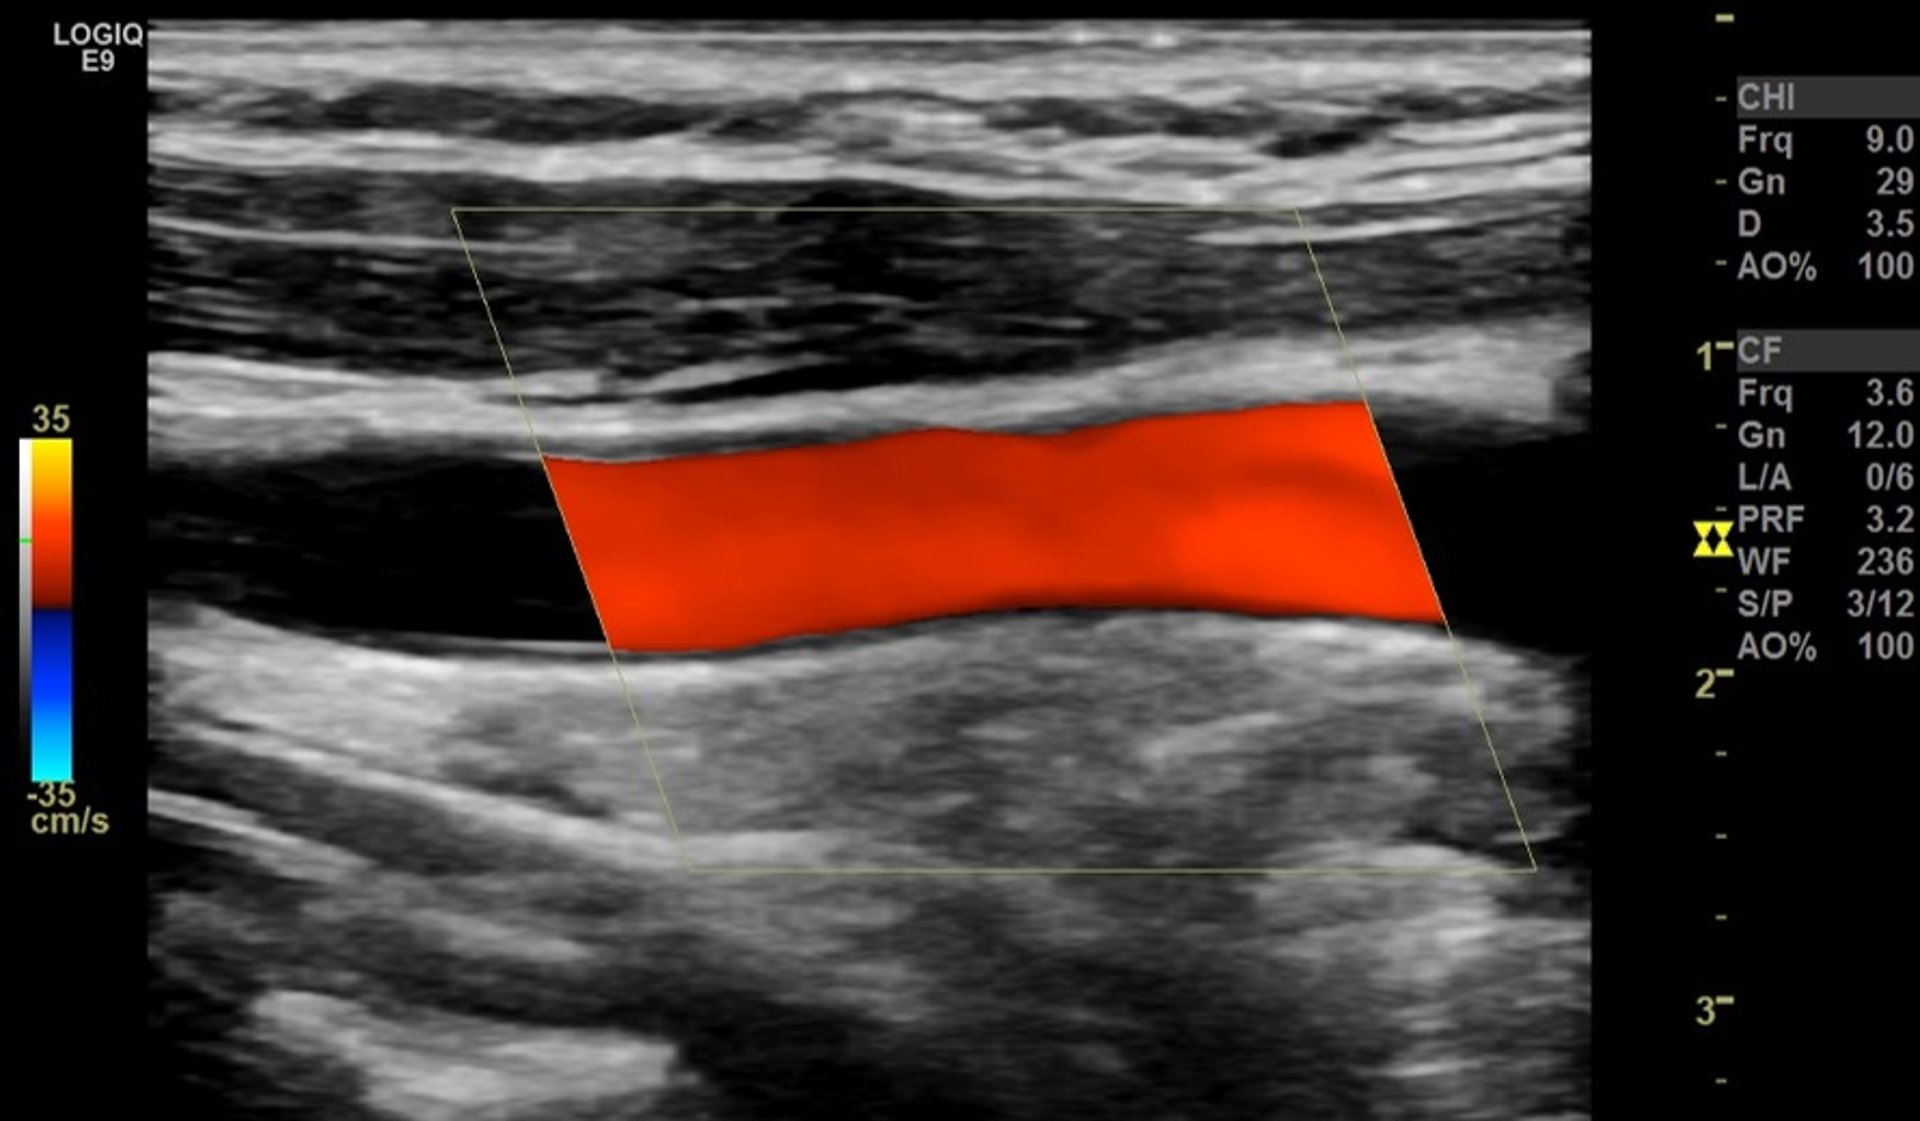

Ultrasound Doppler Berwarna

Untuk ultrasound Doppler berwarna, warna ditempatkan di atas gambar nuansa abu-abu aliran darah yang dihasilkan oleh ultrasound Doppler. Warna menunjukkan arah aliran darah. Merah dapat digunakan untuk mengindikasikan aliran menuju transduser, dan biru dapat digunakan untuk mengindikasikan aliran menjauh dari transduser. Kecerahan warna menunjukkan seberapa cepat darah mengalir.

Ultrasound Doppler Warna dapat membantu menilai risiko stroke karena membantu dokter mengidentifikasi dan mengevaluasi penyempitan atau penyumbatan arteri di leher dan kepala. Prosedur ini berguna untuk mengevaluasi orang yang mengalami serangan iskemik transien atau stroke dan orang yang memiliki faktor risiko aterosklerosis, tetapi tidak memiliki gejala. Ultrasound Doppler Warna juga digunakan untuk menilai aliran darah ke organ internal dan tumor.